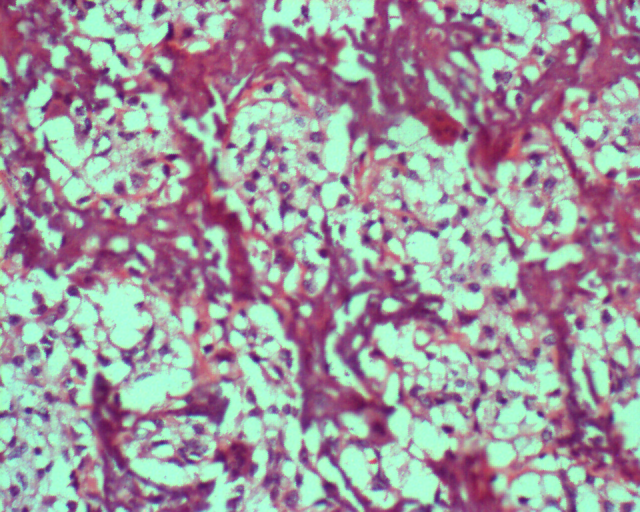

图 6 组织学特点:不规则的肿瘤性骨样基质,基质周围见较多明显异型的成骨细胞,形成肿瘤性成骨的结构。

图 32 组织学特点:在扩张的血管间

见异型成骨细胞,正常的骨小梁

被破坏。